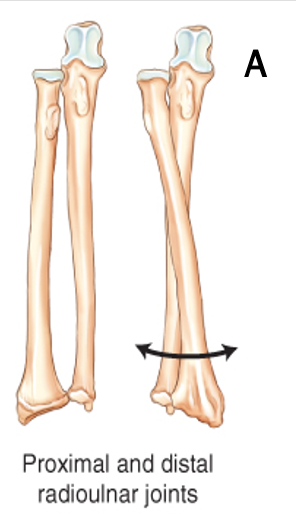

What is the following type of synovial joint?

A

Pivot (trochoid)